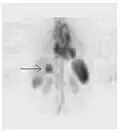

Сканирование паращитовидной железы с помощью ядерной медицины демонстрирует аденому паращитовидной железы, прилегающую к левому нижнему полюсу щитовидной железы. Вышеупомянутое исследование было выполнено с одновременной визуализацией технеция-сестамиби (1-я колонка) и йодом-123 (2-я колонка) и методом вычитания (3-я колонка).

ОФЭКТ-сканирование печени ядерной медицины с мечеными технецием-99m аутологичными эритроцитами. Очаг высокого поглощения (стрелка) в печени соответствует гемангиоме.